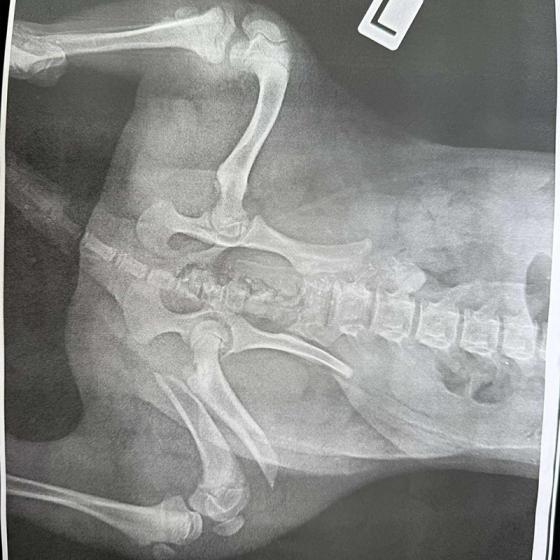

Drobec, ktorý medzičasom dostal meno Gerro, sa napriek všetkému celý čas tešil ľudskej pozornosti a krútil chvostíkom. Má veľmi škaredé zlomeniny prednej aj zadnej labky, pomliaždeniny na celom telíčku, ale našťastie lebka a chrbtica by mali byť v poriadku. Naše srdcia sú z tohto prípadu dolámané tiež na milión kusov, modlíme sa a veríme, že operácie zvládne! My budeme pri ňom a pomôžeme mu vo všetkom, v čom len bude treba.

Momentálne je hospitalizovaný u nášho veterinára, kde ho včera pripravovali na náročné operácie, ktoré by podľa plánov mal podstúpiť dnes. Čaká ho ešte veľmi dlhá cesta, ale pomôžeme mu zvládnuť každý jeden krôčik!